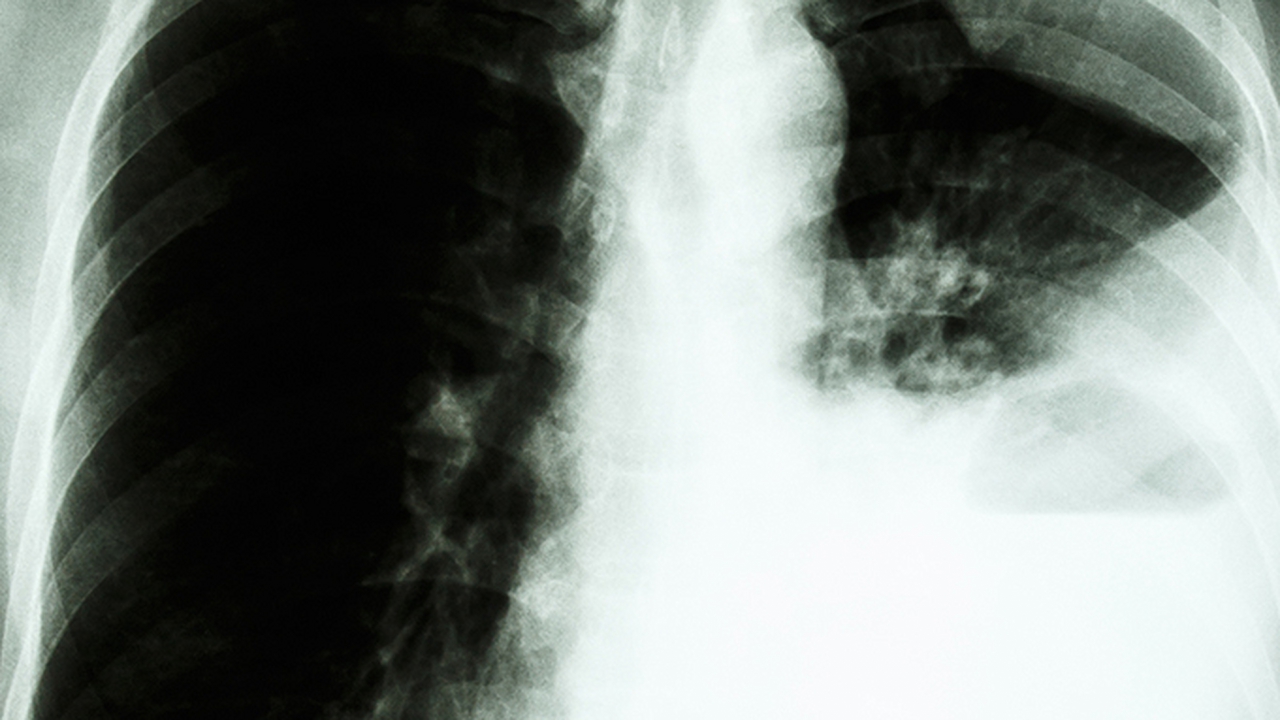

肺癌是一种常见的恶性肿瘤,其发病原因复杂,包括吸烟、空气污染、职业暴露、遗传因素等。早期诊断和规范治疗对提高患者生存率至关重要。目前,肺癌的治疗方法主要包括手术、放疗、化疗、靶向治疗和免疫治疗等。